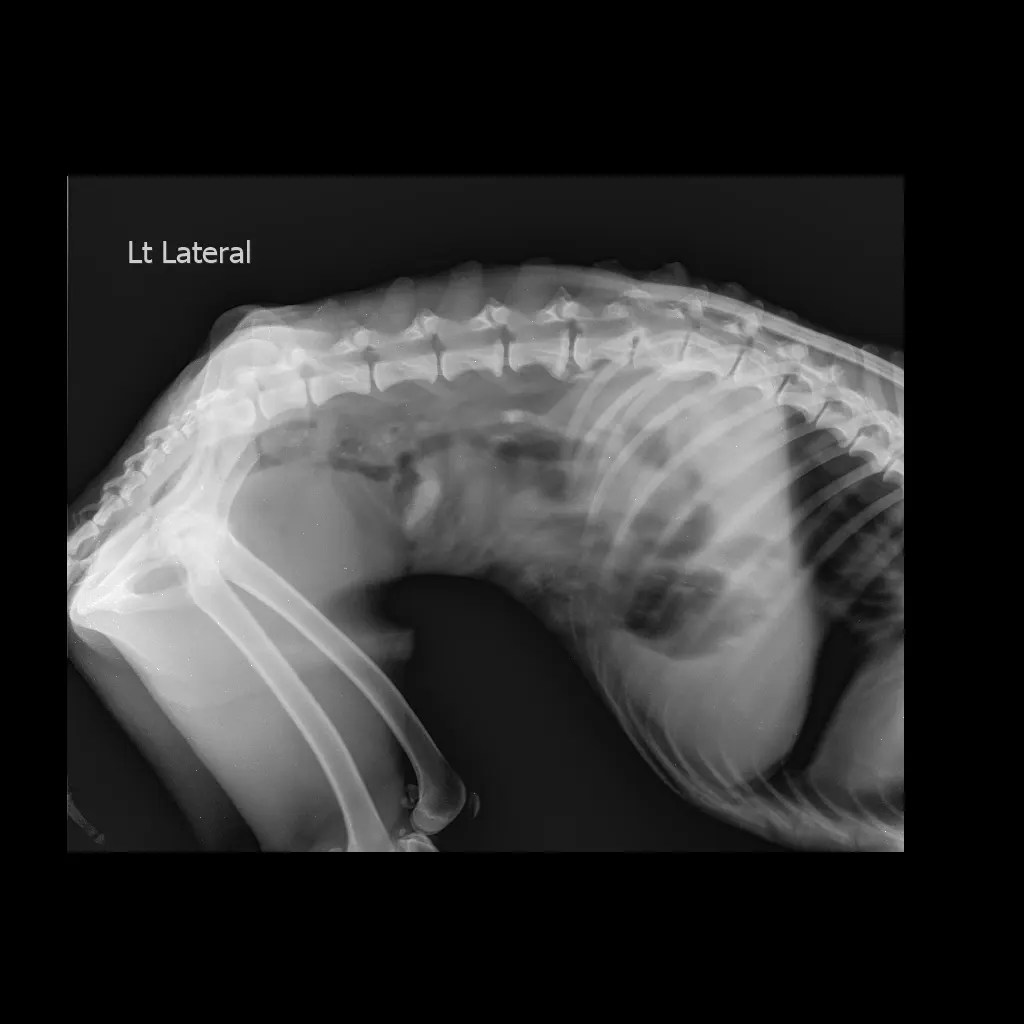

Got him picked up and checked ..a few x-rays done and we got to know he has broken his leg at the hip and ball and socket joint.